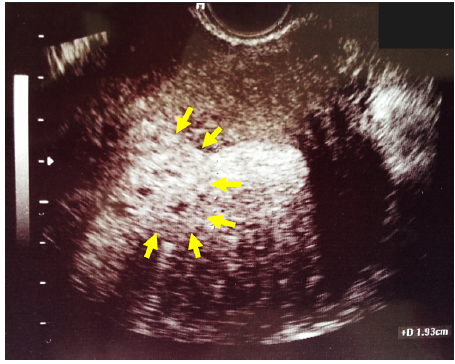

A 40 years old nulliparous patient presented with meno-metrorrhagia and severe dysmenorrhea. A pelvic ultrasound scan revealed the presence of diffuse adenomyosis. At the level of the fundus the endometrial cavity was distorted by a polypoid irregular mass measuring 1.9x1.7x1.5cm (Figure 7). She was scheduled for diagnostic hysteroscopy and laparoscopic management of her adenomyosis.

Figure 7: Ultrasonographic appearance of the 2nd polypoid adenomyoma distorting the fundal area of the cavity (arrows), with associated adenomyotic myometrium.